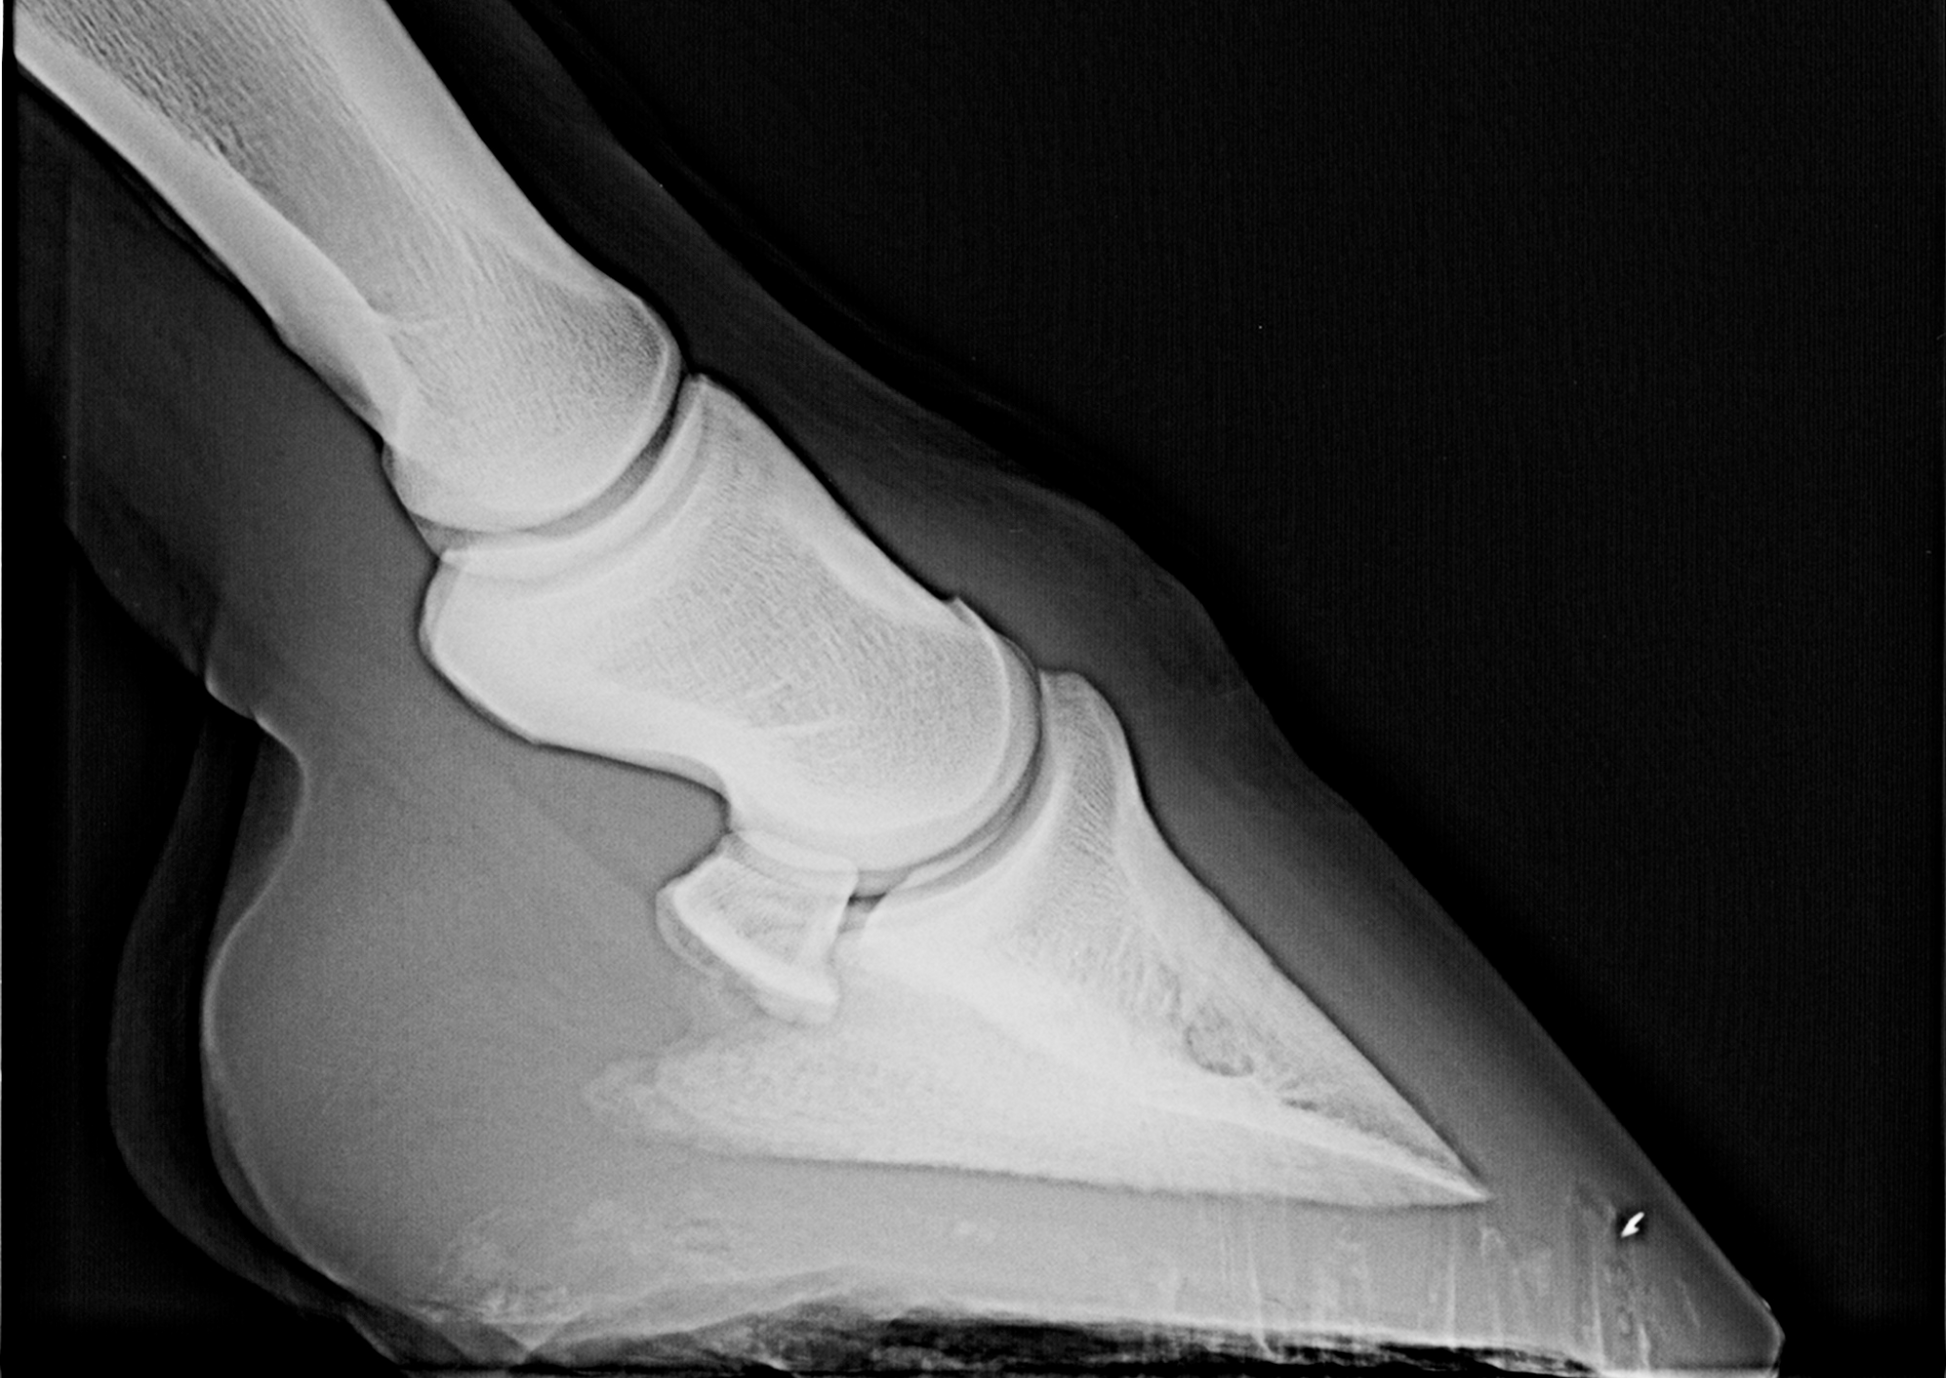

Non conventional radiographic views

Non-conventional radiographic views used in horses, including principles and examples, are discussed and presented.

Speaker: Mr Jonathon Dixon BVetMed MVetMed DipECVDI MRCVS Veterinary Radiologist Rainbow Equine Hospital